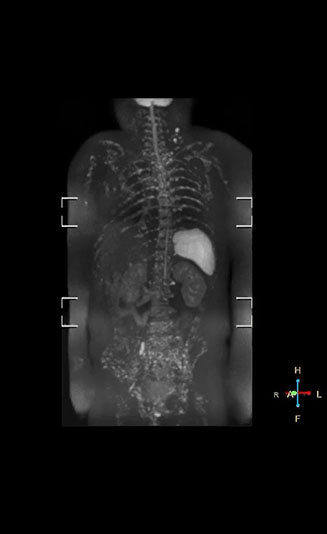

Radiologist Hiroshi Nobusawa, MD, PhD, explains that the coronal DWIBS protocol for whole body DWI is excellent for visualizing lesions in oncology patients. “About 90% of the DWIBS exams are done in this type of patients. The remainder of DWIBS exams are performed to gain information in cases of fevers of unknown origin,” he says. in image acquisition and postprocessing algorithms.”“mDIXON TSE sequences allow simultaneous characterization of morphological changes from the in-phase T2-weighted images and visualization of edematous changes, thanks to the water T2-weighted images from the same acquisition. Anatomical and morphological considerations could be a partial or complete ligament tear, a bony avulsion or hematoma.” “For soft tissue assessment mDIXON brings similar benefits. For example in one T2-weighted mDIXON TSE acquisition, having the multiple contrasts helps us assess abnormalities in peripheral nerves fascicles, which may be due to anatomical or inflammatory changes..” “In peripheral joints, we get good image quality in difficult areas with mDIXON TSE. Fat suppressed images appear homogeneous over the entire image, even with large coverage at 3.0T – for instance in scapular or hip girdles – or in the bearing areas or around metal prostheses*, where fat suppression is often deficient with STIR or spectral fat suppression, causing diagnostic difficulties. If a diagnostic image is right the first time, we don’t need to repeat or add a sequence.” “mDIXON TSE sequences allow simultaneous characterization of morphological changes from the in-phase T2-weighted images and visualization of edematous changes, thanks to the water T2-weighted images from the same acquisition. Anatomical and morphological considerations could be a partial or complete ligament tear, a bony avulsion or hematoma.” “For soft tissue assessment mDIXON brings similar benefits. For example in one T2-weighted mDIXON TSE acquisition, having the multiple contrasts helps us assess abnormalities in peripheral nerves fascicles, which may be due to anatomical or inflammatory changes..”

“The DWIBS sequence’s value in oncology cases is due to the high contrast it creates between lesions and surrounding tissue. Whole body DWI is requested by physicians who need to clarify TNM staging or determine therapeutic strategies, oncologists in need of diagnosis or follow-up scans, surgeons who need to see the presence of distant lesions that are sometimes difficult to detect by CT before surgery, and urologists for the evaluation of bone lesions, and the effect of chemotherapy and radiotherapy.”

“When we limited the scan coverage to the area from neck to femur, we could fit more clinical information in approximately the same scan time. So, we added coronal mDIXON, sagittal T1-weighted, and sagittal STIR sequences to our examination, instead of performing only axial DWIBS and coronal single-shot TSE scans.” The single shot T2-weighted TSE images are used for morphology and compared to DWIBS images to identify T2 shine-through. Sagittal STIR images are used in patients with inflammation or bone metastasis.

“Switching to coronal DWIBS – rather than axial – further shortens scan time,” says Mr. Naka. “Important is that a dS SENSE factor of 5 shortens exam time while high image quality can be maintained, thanks to Ingenia’s dStream architecture.” He adds that the coronal orientation also avoids artifacts that are specific to combining axial images.

“mDIXON FFE allows us to quickly get information we need to assess the presence of fat. That gives us more information when we need to diagnose bone lesions, and when we are asked to judge fat-containing lesions such as hepatocellular or renal carcinoma,” Dr. Nobusawa says. “The mDIXON fat images can help us to differentiate fatty bone marrow from bone lesions. This is especially useful in elderly people, who tend to have fattier bone marrow. The water images provide a high signal-to-noise ratio in the intestinal canal, which is valuable for visualizing lesions in the colon,” he says.

Kawasaki Sawai Hospital’s whole body protocol also includes an mDIXON FFE sequence. Because mDIXON provides images for four contrast types – water only, fat only, in-phase and out-of-phase – from a single acquisition, it is useful in many ways.